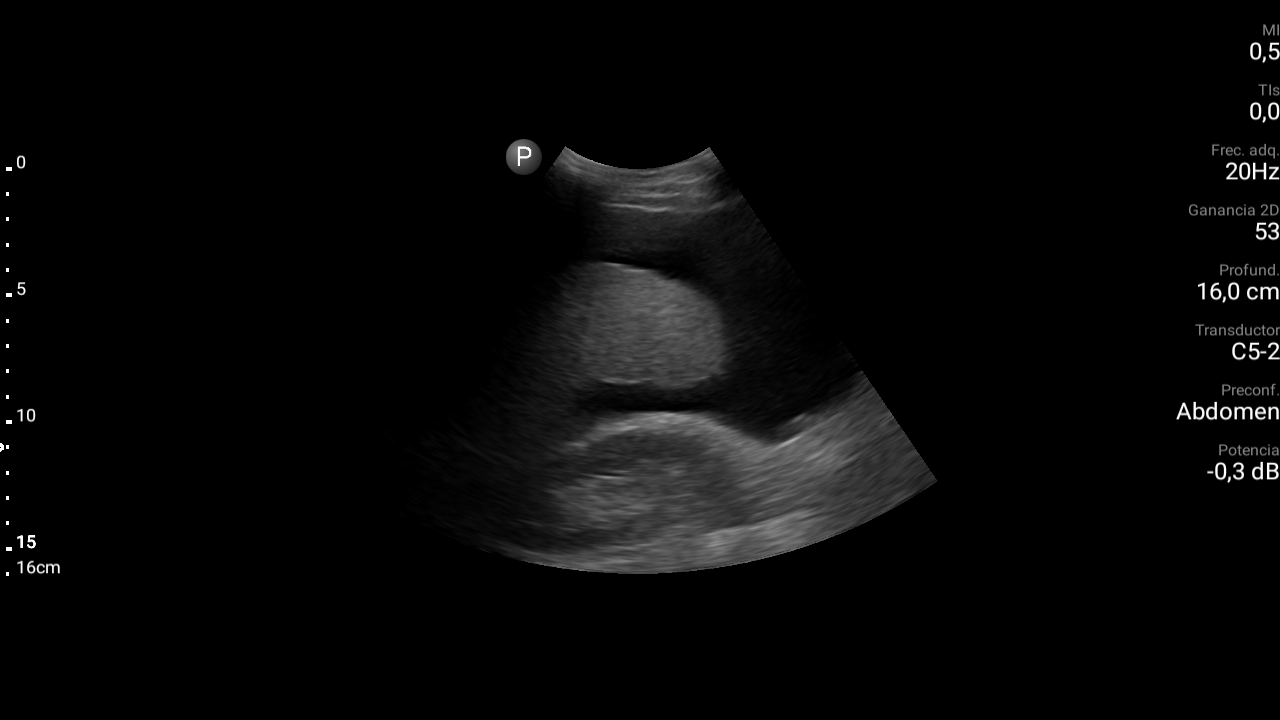

Presencia de ascitis perihepática, periesplénica. En la pelvis se visualizan asas intestinales con aspecto congestivo.

Hígado parcialmente visualizado esteatósico sin lesiones focales.

Derrame pleural bilateral moderado.